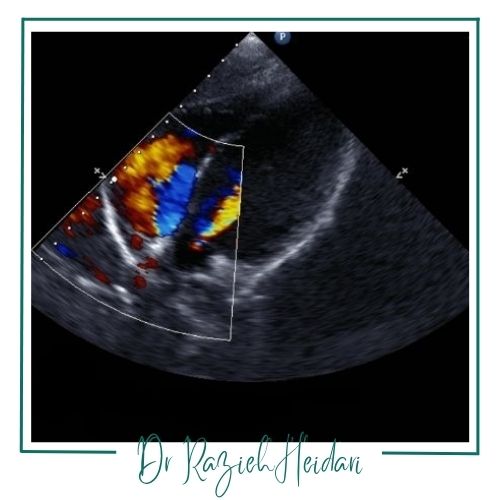

تشخیص ناهنجاریهای قلبی: این شیوه میتواند در تشخیص مشکلات مربوط به قلب مانند نارسایی دریچهها و اختلالات دیگر مفید باشد.

سونوگرافی داپلر رنگی یکی از روشهای تصویربرداری پیشرفته است که با استفاده از امواج صوتی، جریان خون در رگها و بافتهای مختلف بدن را به صورت رنگی نشان میدهد. این تکنیک علاوه بر بررسی ساختار اندامها، امکان ارزیابی دقیقتر خونرسانی را فراهم میکند و به پزشکان در تشخیص بسیاری از بیماریها و تصمیمگیری برای درمان کمک شایانی مینماید. بسته به ناحیه مورد بررسی، این روش در شاخههای مختلفی مانند بررسی جنین، پستان، تیروئید، عروق، کلیهها، اندامها (پا و دست)، کبد و طحال، پیوند اعضا و ... کاربرد دارد که در ادامه به بررسی برخی از مهمترین موارد میپردازیم.